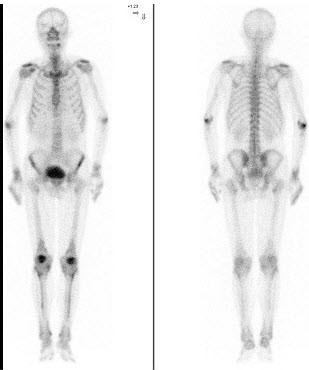

56、单项选择题 正常甲状腺组织摄取碘和高锝酸盐的主要区别是()

A.体内的碘85%集聚在甲状腺

B.锝可以在甲状腺以外组织集聚

C.碘在甲状腺组织可进行有机化,而锝不能